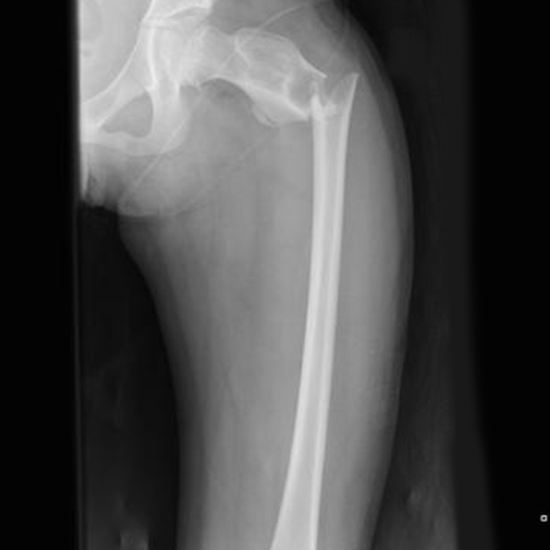

X-Ray Femur AP/Lateral View

On the radiograph of the proximal femur, the bulk of the shaft, pelvic brim, obturator foramen, acetabulum, ischial spine, femoral head, and femoral neck is visible. The knee joint, the proximal tibia and fibula, the femoral condyles and epicondyles, and the distal two-thirds of the femoral shaft are all visible on a distal femur radiograph. To check for signs of disease or injury in the femur, an x-ray femur AP view is performed. It might be gotten if some clinical signs and symptoms point to a bone injury, or if a femur fracture has been partially imaged on a hip or knee X-ray.

This view is useful in assessing:

• Trauma

•  Obvious deformities

•  Suspected foreign body

• Inability to weight bear

•  Osteomyelitis

• Fracture